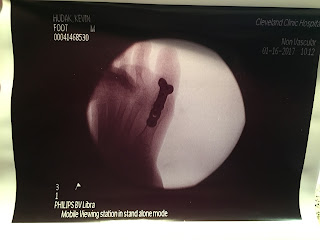

For the surgeon and medical team for taking good care of Kevin.